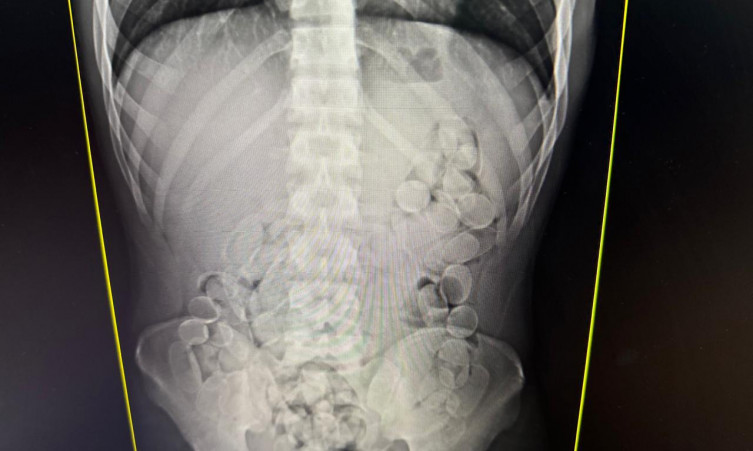

Nesta fiscalização de bagagens, foram encontradas 50 cápsulas de cocaína e os cães farejadores indicaram a presença de drogas com mais dois passageiros. Diante da suspeita de que poderiam ter engolido cápsulas da droga, duas mulheres e um homem, foram encaminhados à Santa Casa para exames de raio-x e expelir o entorpecente. Posteriormente, os três confessaram ter ingerido aproximadamente 100 cápsulas cada um. Foram cerca de quatro quilos de cocaína apreendidos.A Operação Fronteira RFB, assim como as demais ações realizadas pela Receita Federal em parceria com outras instituições, tem como foco combater a concorrência desleal com a indústria nacional e os importadores regulares, evitar a sonegação de impostos e impedir a entrada de produtos que não atendem às normas de segurança no país, além de combater o tráfico de drogas.